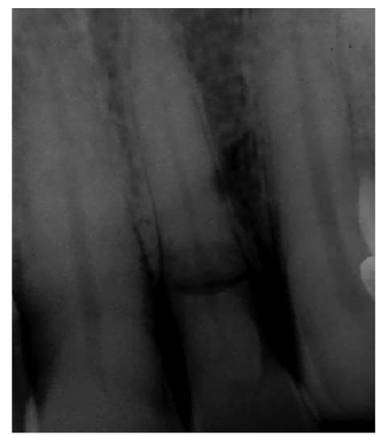

plane (Figure 19-48). The preoperative radiograph(s)

and careful probing with a periodontal probe around the cervical area of the

tooth will give some indications.

Figure 19-48: Mesially inclined mandibular second molar. Because of the tilt, the direction of the bur should be angled toward the distal to avoid a perforation during access cavity preparation.